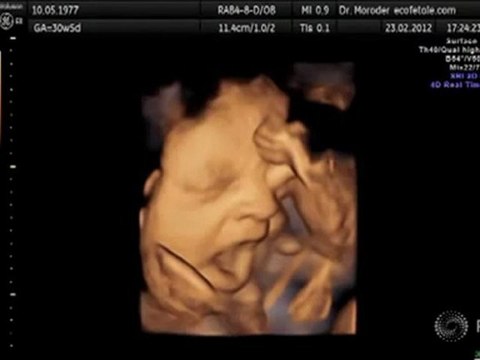

This viral video shows how active unborn babies can be in the womb and it's a lot of fun for expectaThis video of an unborn baby has had more than six million views - because the little one looks like it's DANCING in the womb. The amazing footage is from a 4D ultrasound scan - and it really looks like the foetus is bopping away inside its expectant mum , although no more is know about her identity. Originally shared on medical social network Meddy Bear's Facebook page on December 19, it came from the site in Ukraine, where doctors, nurses and medical staff can post unusual, entertaining or interesting news about their roles. While many of us are familiar with 3D ultrasound images which show still images of unborn babies , 4D scans can show moving 3D images. Read more: Heartwarming picture shows 'angel' watching over unborn baby in ultrasound scan The foetus is seen in a variety of positions, moving its limbs and even kicking out against the womb, before giving what looks like a big yawn.nt parents to watchThe Facebook response to the post has been colossal, with many remarking on how much the 4D scan can show expectant parents. Connie Girlando wrote: Wow, 4D ultrasound, that's beyond amazing... to think that is all they know. Facebooker Kirsty Hartley added: Wow! Freaks me out a little bit to see how much the baby moves (not had one yet) but also amazing.